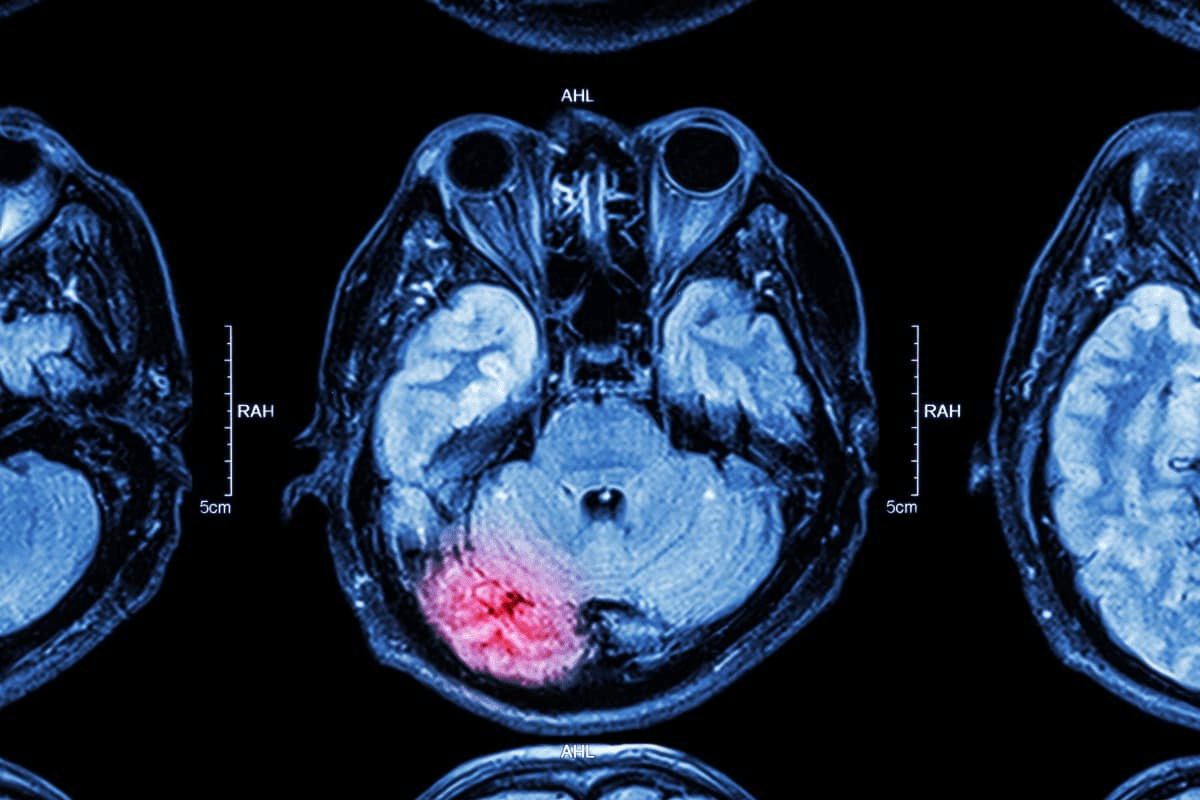

Advanced Imaging Techniques: CT, MRI, and PET

When Advanced Imaging Is Necessary

Doctors often use advanced imaging when they think there might be complications. For example, CT scans help see if thyroid cancer has spread to lymph nodes. They’re also good for checking on goiters that are below the sternum.

Comparing Effectiveness Across Modalities

Each imaging method has its own benefits. CT scans show the thyroid’s shape and how it fits with other parts of the body. MRI is better at showing soft tissues, which is helpful for thyroid cancer checks. PET scans are great for spotting cancer cells because they show how active they are.